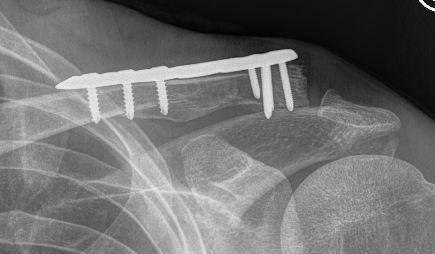

Dorsal locking plate +/- CCL reconstruction

Advantage

No need to remove

Disadvantage

Lateral screws under significant tension and subsequently higher rate of screw/plate pull-out

Indication

Sufficient lateral bone to obtain fixation

Consider having hook plate available / supplement with coraco-clavicular fixation

Dorsal locking plate with cerclage fibretape

- precontoured distal locking plate in 35 patients

- all united at mean of 4 months

- excellent outcomes scores

Xu et al BMC Musculoskeletal Disorders 2019

- 16 patients with locking plate versus 18 with plate + CC suture anchors

- shorter union time (14 v 16 weeks) and better outcomes (94 v 90 Constant) with suture anchors